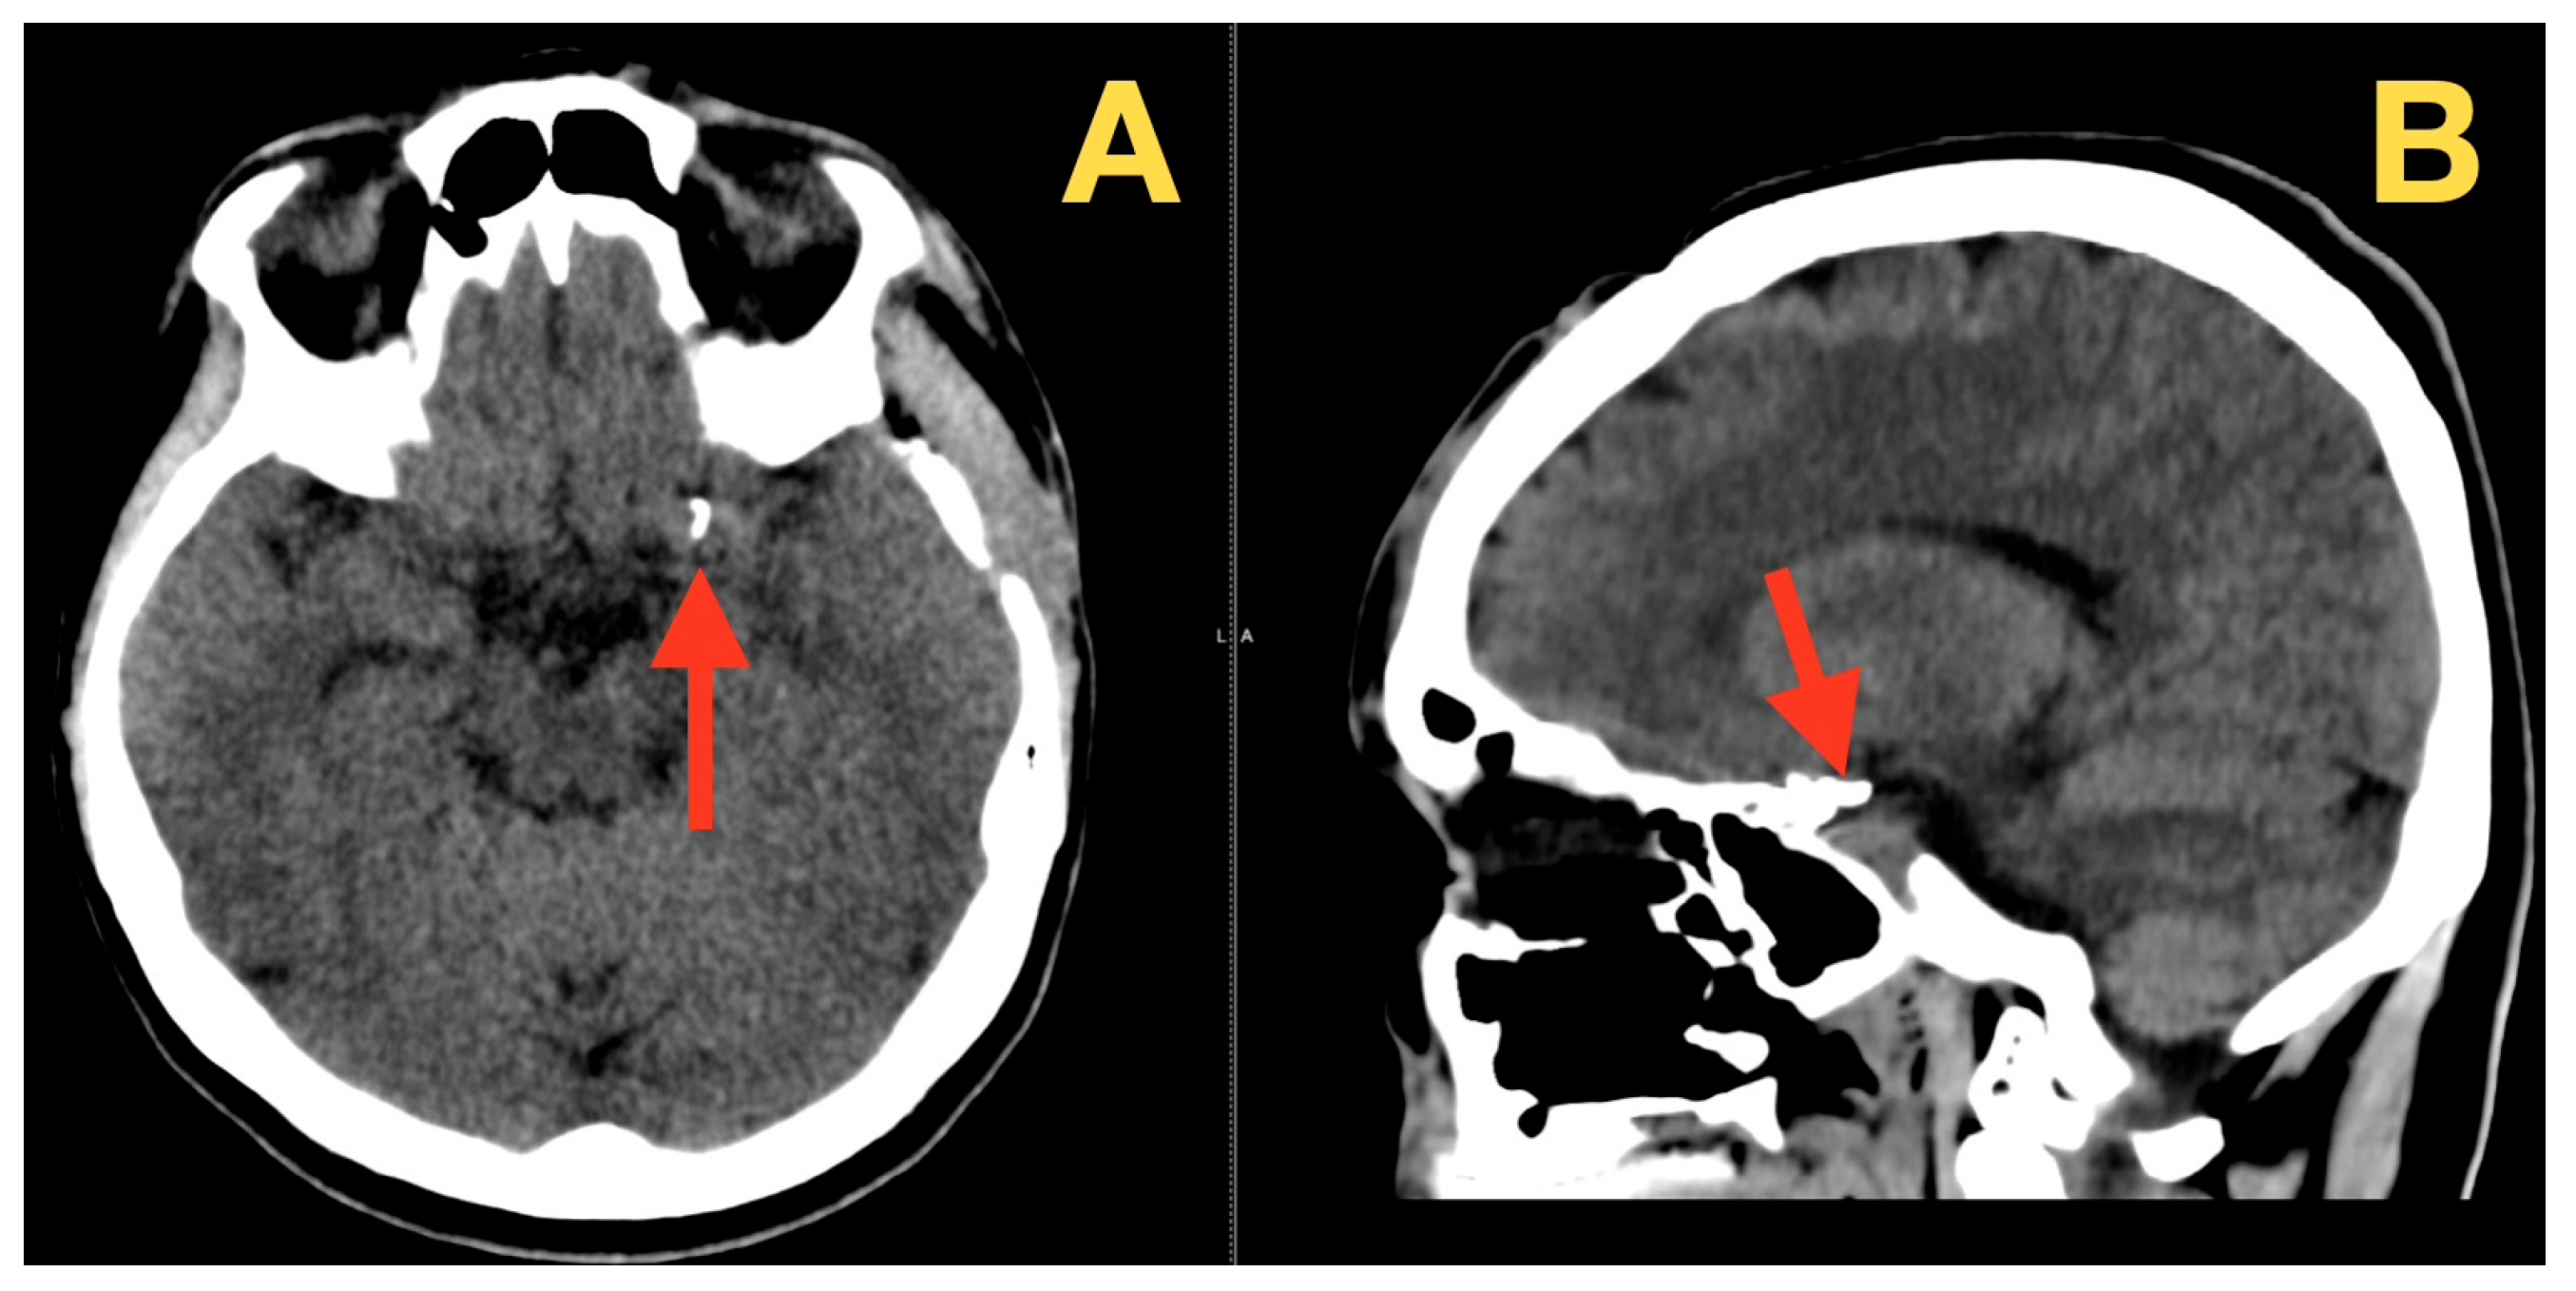

2. Case Presentation